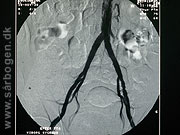

Før PTA af iliacakar...

Zoom

Under PTA af iliacak...

Efter PTA af iliacak...